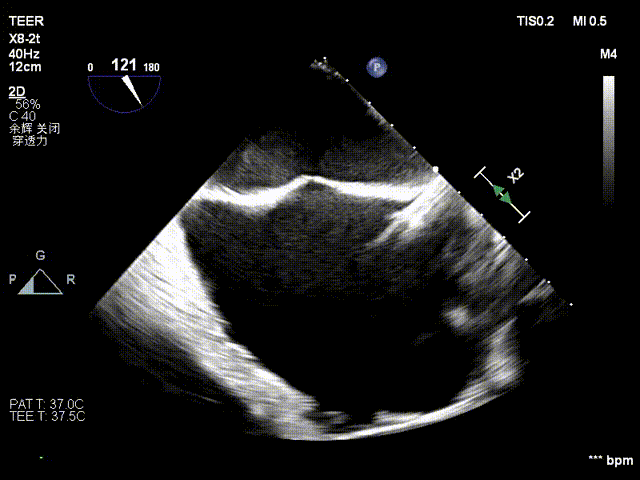

图3:房间隔可用高度>4cm

TEER手术过程

患者全麻下行TEER手术。向睿副主任团队穿刺患者右侧股静脉,在X线及食道超声指导下完成房间隔穿刺(视频4)成功获得3.95cm穿刺高度(图4)。再将加硬导丝送至左上肺静脉,20F股静脉扩张鞘充分扩张股静脉穿刺部位,沿加硬导丝将可操纵导引导管(SGC)送入左房。延SGC送入XTR夹子完成骑跨,使用M旋钮使夹子指向二尖瓣(图5)(视频5)。调整Mitraclip输送系统顺利到达二尖瓣目标位置,TEE指导下左房内完成弹道测试和Orientation调整(视频6)。缓慢将XTR夹子送入左室,并三维再次确认夹子轴向和反流位置,缓慢上提夹子使夹臂成功捕获瓣叶(视频7),Gripper Down夹持前后瓣叶并缓慢关闭夹臂(视频9),夹持后反流降至微量(视频10),二尖瓣平均跨瓣压差2mmHg(图6)。评估后将夹子释放。释放后反流微量夹子稳定。术后复查超声证实夹合组织充分,显示微量残余分流。术后二尖瓣平均跨瓣压差2mmHg,肺静脉多普勒波形恢复正常。手术时间持续约1.5小时。

图4:穿刺高度3.95cm